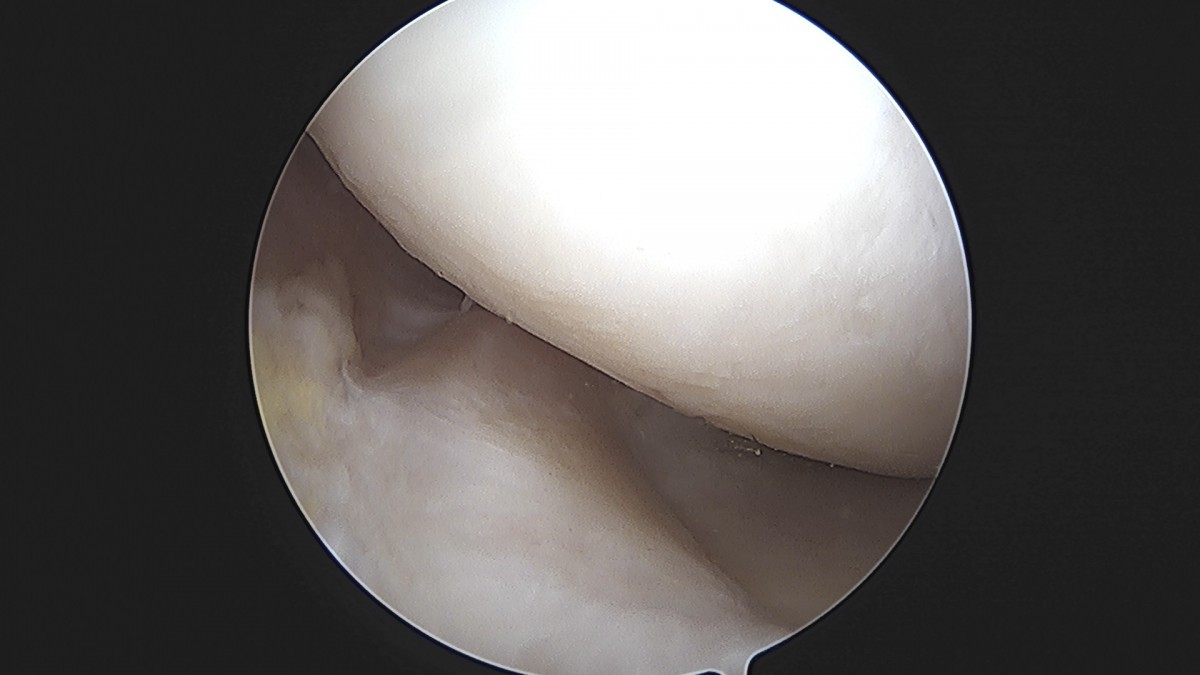

이재상원장님 무릎 반월상 연골판 절제술 최용O 환자

작성자 최고관리자 댓글 0건 조회 379회 작성일 25-09-16 15:57